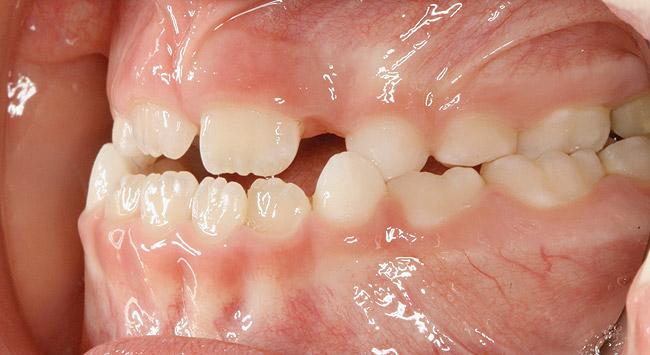

(14.) Angle Class III occlusion with constricted maxilla.

Figure 14